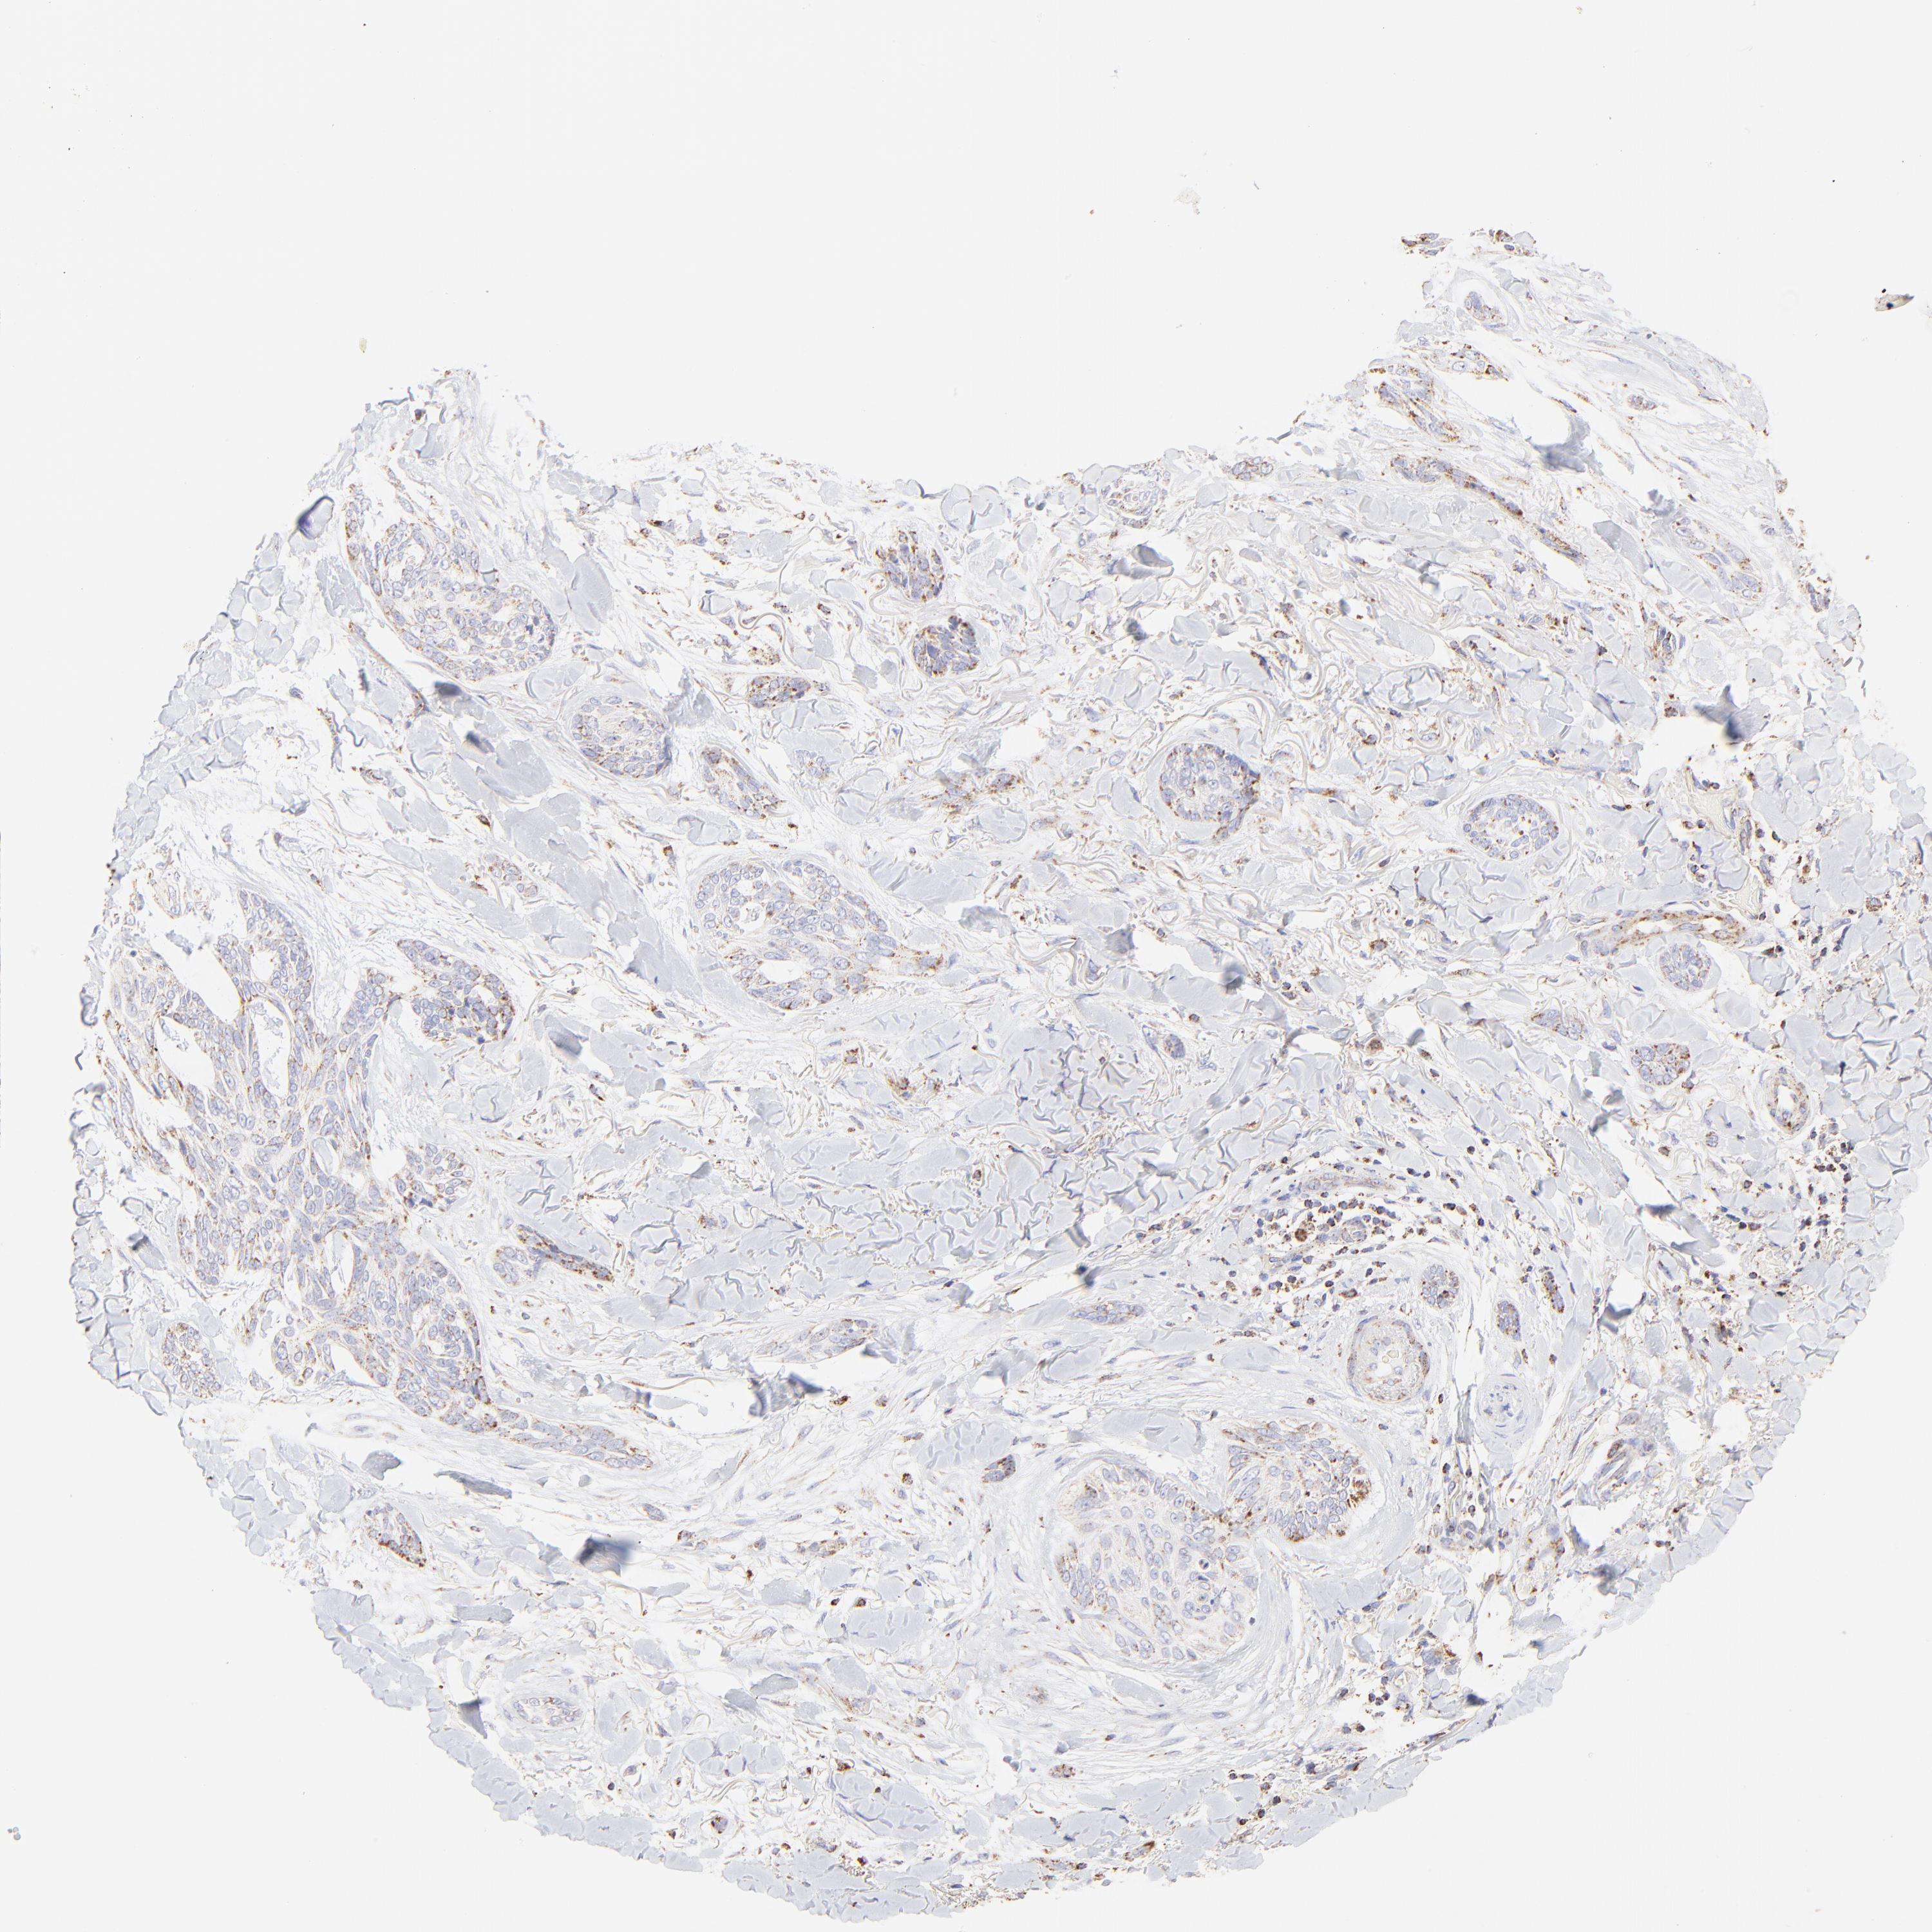

SKIN CANCER - Protein expressioni

A mouse-over function shows sample information and annotation data. Click on an image to view it in a full screen mode. Samples can be filtered based on level of antibody staining by selecting one or several of the following categories: high, medium, low and not detected. The assay and annotation is described here.

Antibody stainingi

Antibody staining in the annotated cell types in the current human tissue is reported as not detected, low, medium, or high, based on conventional immunohistochemistry profiling in selected tissues. This score is based on the combination of the staining intensity and fraction of stained cells.

Each image is clickable and will lead to virtual microscopy that enables deeper exploration of all samples and also displays staining intensity scores, fraction scores and subcellular localization as well as patient and tissue information for each sample.

Antibody HPA002907

Antibody HPA005835

Staining

High

Medium

Low

Not detected

Intensity

Strong

Moderate

Weak

Negative

Quantity

>75%

75%-25%

<25%

None

Location

Nuclear

Cytoplasmic/membranous

Cytoplasmic/membranous,nuclear

Squamous cell carcinoma, NOS

Basal cell carcinoma